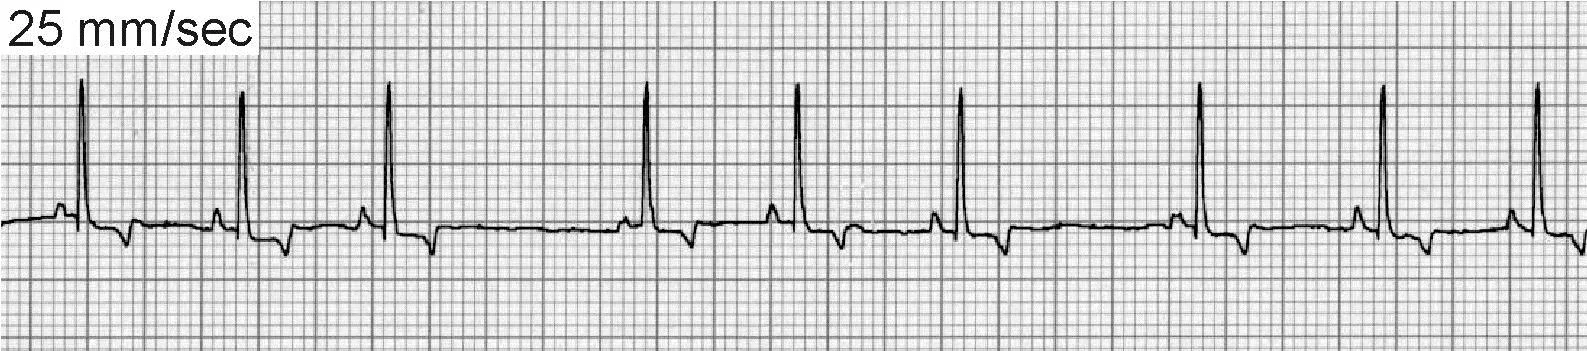

Accelerated Idioventricular Rhythm

Also known as slow ventricular tachycardia (Figure 4), this is a unique form of ventricular tachycardia typified by slow heart rates (dogs, 70–150 bpm). The rate of the accelerated idioventricular rhythm is usually within 10 to 15 beats of the normal sinus rate, and control of the heart rhythm alternates between the two sites. Because the rate of the idioventricular focus is slow, there is little hemodynamic consequence and patients generally remain asymptomatic. These rhythms are commonly seen with noncardiac disease and also in dogs with traumatic myocarditis and neurologic disease. Specific treatment of an accelerated idioventricular rhythm is rarely indicated and should be directed toward underlying causes.

ECG of accelerated idioventricular rhythm, or slow ventricular tachycardia